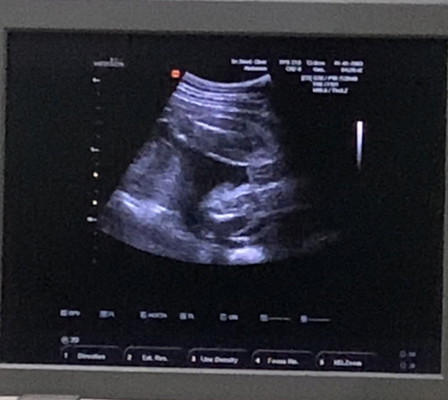

อยากถามแม่ๆหน่อยค่ะ

อันนี้ผู้หญิงหรือผู้ชายคะ ดูไม่ค่อยเป็นค่ะ